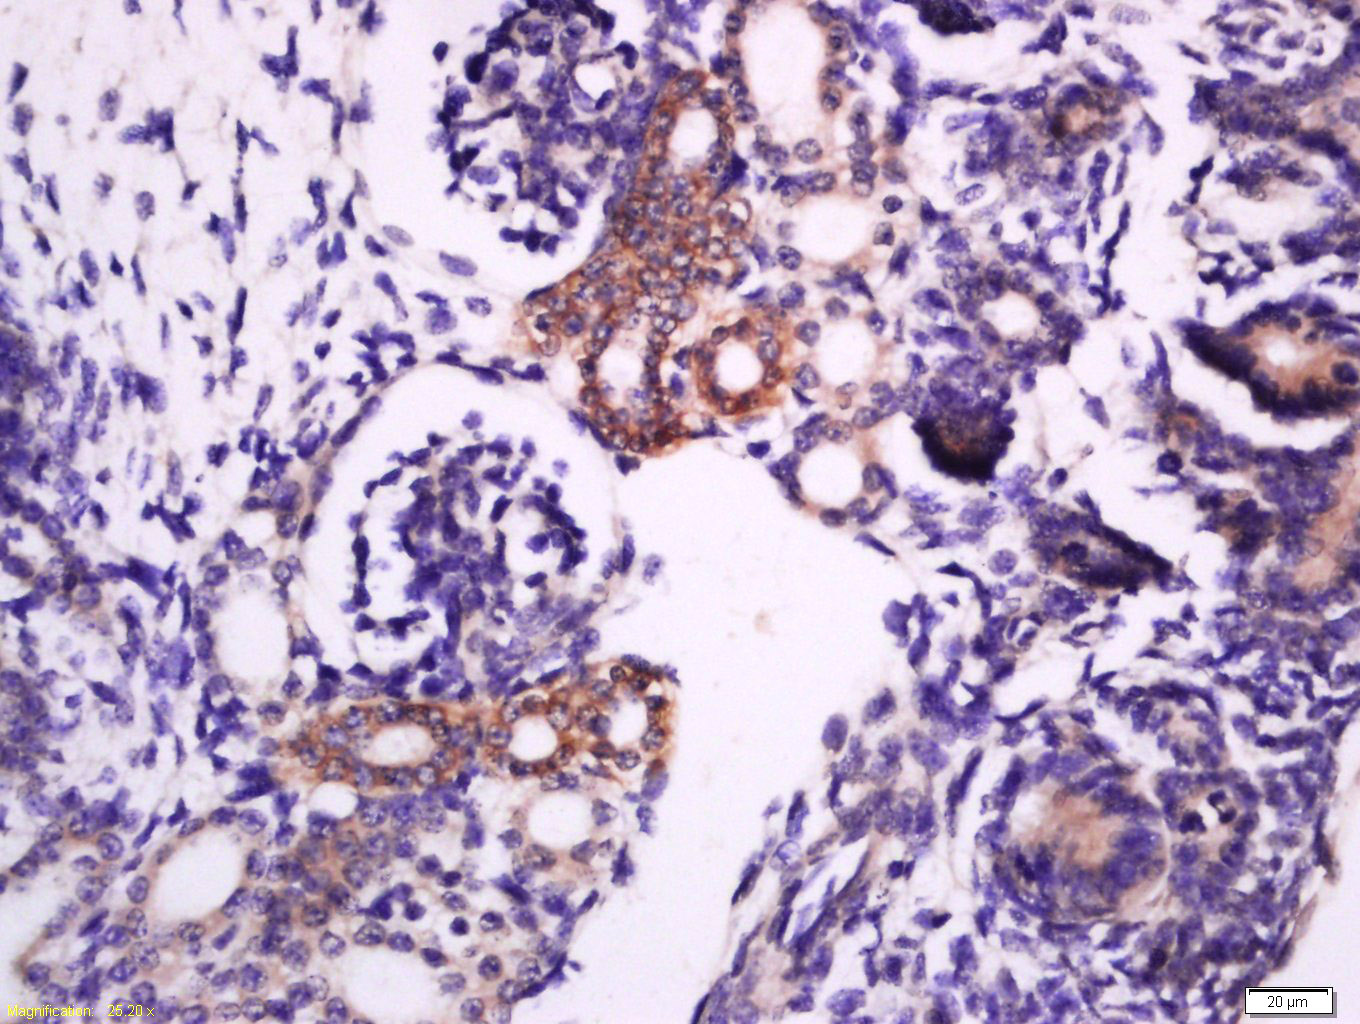

Tissue/cell: Mouse embryo tissue; 4% Paraformaldehyde-fixed and paraffin-embedded; Antigen retrieval: citrate buffer ( 0.01M, pH 6.0 ), Boiling bathing for 15min; Block endogenous peroxidase by 3% Hydrogen peroxide for 30min; Blocking buffer (normal goat serum,C-0005) at 37℃ for 20 min; Incubation: Anti-Syntaxin 1a Polyclonal Antibody, Unconjugated(bs-10315R) 1:200, overnight at 4°C, followed by conjugation to the secondary antibody(SP-0023) and DAB(C-0010) staining